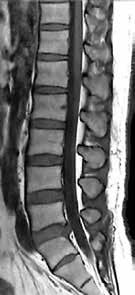

Ziel der Forschungen an der Universität Bordeaux war die hochaufgelöste und detailreiche Darstellung spezieller Hirnareale, wie des Hippocampus oder des Claustrum. Diese Regionen hatte Prof. Tourdias schon am 7T-System bei seinem Aufenthalt an der Stanford-Universität studiert. Nun war es mit der AiCE-Technologie möglich, vergleichbar aufgelöste Bilder auch bei 3T in akzeptabler Untersuchungszeit zu erzeugen (siehe Abb. 5 a und b).

Natürlich lassen sich die Vorteile einer höheren Auflösung nicht nur in der klinischen Forschung nutzen, sondern sind auch dazu geeignet, bei-

Abb. 5 a + b: Hochaufgelöstes Bild des Hippocampus; 0,15 mm x 0,15 mm; 2 mm Schichtdicke; rechts mit AiCE-Rekonstruktion. Mit freundlicher Genehmigung des Unversitätsklinikums Bordeaux. Abb. 6 a + b: Hochaufgelöstes Bild des Knies; 0,15 mm x 0,15 mm (interpoliert); 1 mm Schichtdicke; rechts mit AiCE-Rekonstruktion.